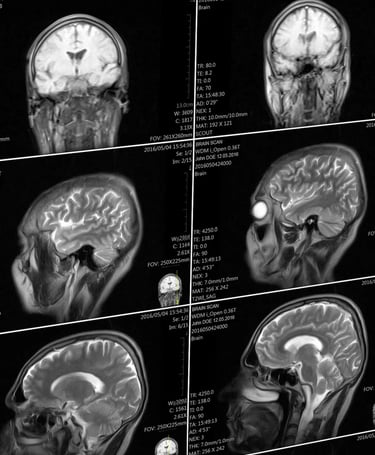

Microwave Effects on the Human Body

Introduction: Swanson et al. (1) examined 24 US Cuban embassy personnel exposed to an unknown directed energy source. They found that 21 of those examined had clinical findings similar to mild traumatic brain injury (mTBI). All 24 individuals reported audible and sometimes painful sounds during possible exposures. Hoffer et al. (2) examined a partially overlapping group of 35 embassy-related individuals, among whom 25 reported auditory phenomena and post incident symptoms along with 10 individuals who lived with the affected persons who did not report hearing sounds. These workers found that all 25 individuals hearing sounds had vestibular abnormalities; over half of these exhibited cognitive disorders. The ten individuals who did not report hearing sounds did not exhibit vestibular or cognitive abnormalities. Verma et al. (3) expanded Swanson's 2018 report to include 40 government employees describing acoustic experiences. These individuals had neurological symptoms suggesting mTBI. Significant brain structural abnormalities were documented using advanced specialized MRI imaging of this cohort (3).

"The analysis found that the patients who had been stationed in Cuba had less volume of white matter, which contains the parts of neurons that connect brain regions together, than the control groups. They had differences in their cerebellum to the control groups, and had lower connectivity in the auditory and visual networks of the brain (though not those involved in executive function).

Notably, Verma says, the patterns of changes in brain volume and in the cerebellum, were unlike the patterns of changes seen in any other diseases—they didn’t look like the changes seen in patients with traumatic brain injuries, for example, or other neurological conditions. “To the best of my knowledge, this is something unique to these patients,” she says. Seeing a new pattern, she says, is extremely rare.

The findings do indicate, though, that there are structural and functional changes in the brain that offer a potential basis for clinical symptoms. It’s a counter to some criticisms levied on the team’s prior paper that evaluated the neurological symptoms of this patient group, which included skepticism that their experiences weren’t just psychogenic. “The clinical element said there should be a problem in the cerebellum, and the imaging showed changes in the cerebellum. It’s an objective measure,” Verma says.

However, it’s not clear what the overall changes seen in this study mean clinically, for patient function, according to an accompanying editor’s note also published in the JAMA. It’s also not clear how significant the changes between the two groups are, says Gerard Gianoli, a neurotologist (someone who specializes in neurological disorders of the ear) at the Ear and Balance Institute in Louisiana. Gianoli says he’s more convinced by a 2018 paper that showed inner ear damage in those affected. The new paper, though, still provides important data. “It’s a part of the puzzle, and it adds a piece of information,” he says.

The changes in these patients, both in the brain and in the inner ear, could be caused by multiple different things, Gianoli says—this research doesn’t answer questions about the initial trigger. It may never be clear what happened, Verma says. “If you asked me, did something happen, I would say yes. But this doesn’t tell us how or why.” Americans reported hearing torturous sounds in Cuba—and now their brains seem changed.

NIH studies find severe symptoms of “Havana Syndrome,” but no evidence of MRI-detectable brain injury or biological abnormalities, Monday, March 18, 2024, National Institutes of Health (NIH)-https://www.nih.gov/news-events/news-releases/nih-studies-find-severe-symptoms-havana-syndrome-no-evidence-mri-detectable-brain-injury-or-biological-abnormalities

"Using advanced imaging techniques and in-depth clinical assessments, a research team at the National Institutes of Health (NIH) found no significant evidence of MRI-detectable brain injury, nor differences in most clinical measures compared to controls, among a group of federal employees who experienced anomalous health incidents (AHIs). These incidents, including hearing noise and experiencing head pressure followed by headache, dizziness, cognitive dysfunction and other symptoms, have been described in the news media as “Havana Syndrome” since U.S. government personnel stationed in Havana first reported the incidents...“It is possible that individuals with an AHI may be experiencing the results of an event that led to their symptoms, but the injury did not produce the long-term neuroimaging changes that are typically observed after severe trauma or stroke. We hope these results will alleviate concerns about AHI being associated with severe neurodegenerative changes in the brain.”